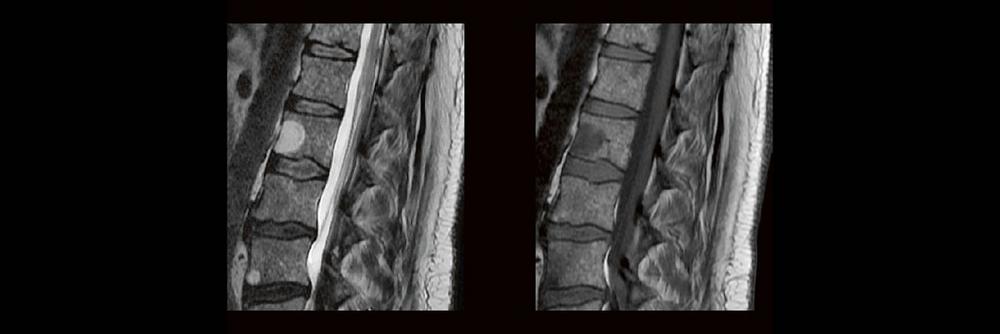

Dual-Energy CT der Wirbelsäule: Technik und klinische Praxis (Webinar | Online)

Professor Dr. med. Matthias PumbergerPD Dr. med. Torsten Diekhoff Die Dual-Energy-Computertomographie (DECT) hat für viele klinische Anwendungen bereits Einzug in die Praxis genommen. Für die […]